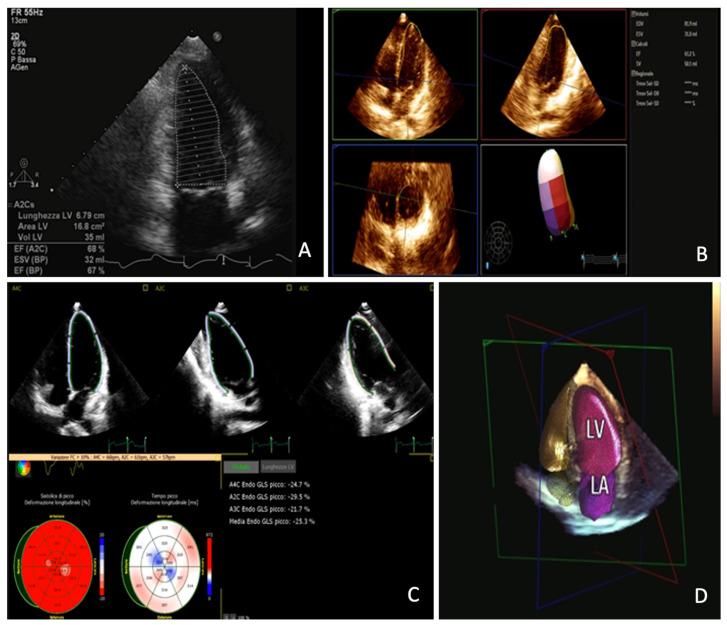

缺血性慢性心肌病的多模态成像

Multimodality Imaging in Ischemic Chronic Cardiomyopathy.

Ischemic chronic cardiomyopathy (ICC) is still one of the most common cardiac diseases leading to the development of myocardial ischemia, infarction, or heart failure. The application of several imaging modalities can provide information regarding coronary anatomy, coronary artery disease, myocardial ischemia and tissue characterization. In particular, coronary computed tomography angiography (CCTA) can provide information regarding coronary plaque stenosis, its composition, and the possible evaluation of myocardial ischemia using fractional flow reserve CT or CT perfusion. Cardiac magnetic resonance (CMR) can be used to evaluate cardiac function as well as the presence of ischemia. In addition, CMR can be used to characterize the myocardial tissue of hibernated or infarcted myocardium. Echocardiography is the most widely used technique to achieve information regarding function and myocardial wall motion abnormalities during myocardial ischemia. Nuclear medicine can be used to evaluate perfusion in both qualitative and quantitative assessment. In this review we aim to provide an overview regarding the different noninvasive imaging techniques for the evaluation of ICC, providing information ranging from the anatomical assessment of coronary artery arteries to the assessment of ischemic myocardium and myocardial infarction. In particular this review is going to show the different noninvasive approaches based on the specific clinical history of patients with ICC.

摘要

缺血性慢性心肌病(ICC)仍然是导致心肌缺血、梗死或心力衰竭的最常见心脏疾病之一。多种成像方式的应用可以提供有关冠状动脉解剖结构、冠状动脉疾病、心肌缺血和组织特征的信息。特别是,冠状动脉计算机断层扫描血管造影(CCTA)可以提供有关冠状动脉斑块狭窄、其成分的信息,以及使用血流储备分数CT或CT灌注对心肌缺血进行可能的评估。心脏磁共振成像(CMR)可用于评估心脏功能以及缺血的存在。此外,CMR可用于表征冬眠或梗死心肌的心肌组织。超声心动图是获取心肌缺血期间心脏功能和心肌壁运动异常信息最广泛使用的技术。核医学可用于定性和定量评估灌注。在本综述中,我们旨在概述用于评估ICC的不同无创成像技术,提供从冠状动脉解剖评估到缺血心肌和心肌梗死评估的信息。特别是,本综述将展示基于ICC患者特定临床病史的不同无创方法。